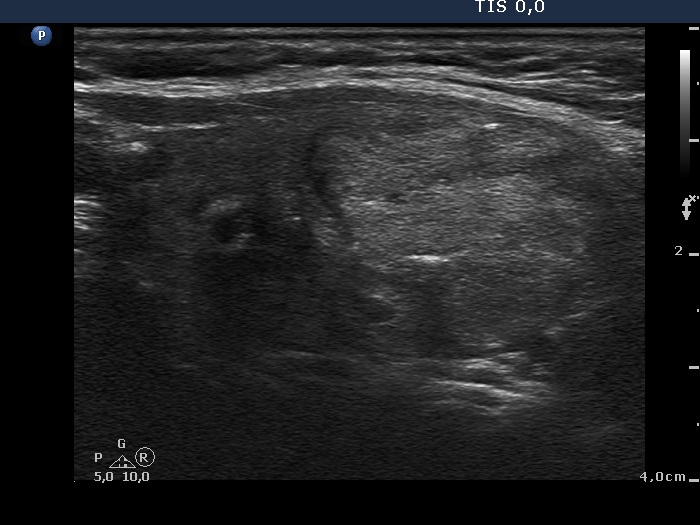

Benign hyperplastic nodule (histological diagnosis) - case cons039

|

Two foci of coarse calcification are presented, one in the left horizontal and another one in the right longitudinal scan.